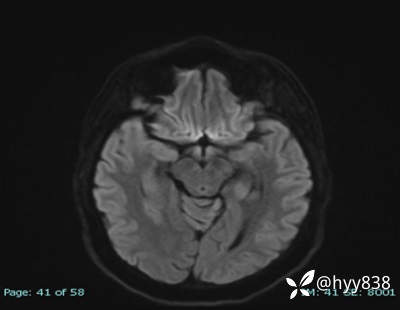

DWI